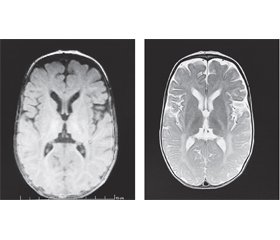

У віці 5 місяців пацієнтці були проведені дослідження: МРТ головного мозку та ЕЕГ-відеомоніторинг. Результати подані в табл. 2.

У семимісячному віці дитині було зроблено повторне МРТ-дослідження головного мозку з наступним висновком: на тлі дифузних помірно виражених атрофічних змін паренхіми півкуль головного мозку простежуються великі ділянки гіпо/демієлінізації в ділянці базальних ядер, у перивентрикулярних відділах із поширенням по білій речовині напівовальних центрів до субкортикальних відділів потиличних, тім’яних, дещо менше — скроневих і лобових, «тигроїдного» рисунка. Візуалізується виражене уповільнення дифузії у проєкції кортикоспінальних трактів обох півкуль головного мозку. Крім того, на тлі зменшення в обсязі паренхіми мозочка визначаються симетричні хмароподібні ділянки демієлінізації на рівні середніх ніжок мозочка, біля зубчастих ядер. Потовщення хіазми та проксимальних сегментів зорових нервів. Явища замісної вентрикулодилатації. МР-картина може відповідати нейродегенеративному процесу (МР-картина суспектна синдрому Crabbe та MLD) (рис. 1).